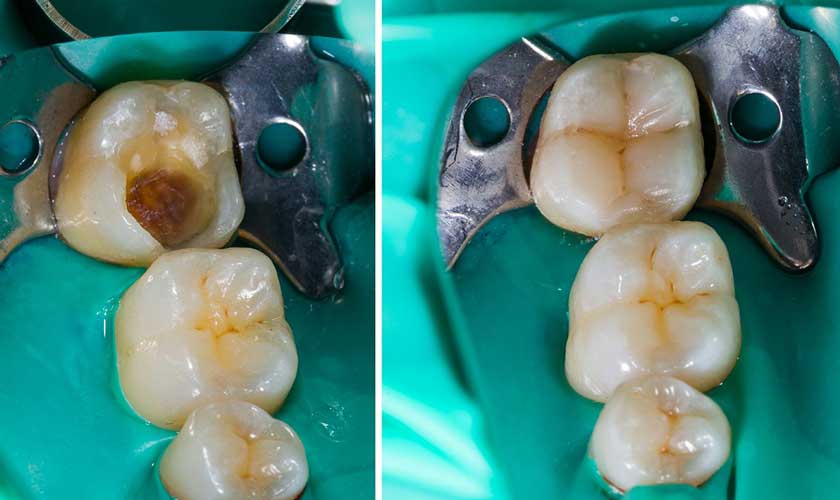

- Trám răng: Trám răng được áp dụng trong trường hợp sâu men răng hoặc sâu ngà răng, chưa tổn thương tủy răng. Bệnh nhân sẽ được loại bỏ mô răng bị sâu và sử dụng vật liệu trám thẩm mỹ để trám bít hố rãnh do sâu răng gây ra.

Trước và sau điều trị sâu răng